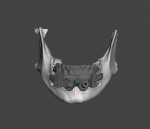

The laboratory technician then imported the CBCT data into the dynamic navigation treatment planning software (X-Guide, X-Nav Technologies). The intraoral scans were aligned with the CBCT data, and the dental implants were planned in a restoratively driven manner. The virtual treatment plant was then exported from the software and imported into dental CAD software (DentalCAD, exocad). The technician designed the provisional prosthesis, and the implants were verified to be in suitable positions. Using a combination of other CAD software modules, the technician designed a foundation guide, occlusal positioning jig, and provisional prosthesis. The foundation guide included an attachment arm for the dynamic navigation patient tracker array (Figure 1). The foundation guide was designed to allow its superior edge to act as a bone reduction reference and two-guide tube for fixation screws. The fixation screw positions were designed to not intersect with the planned implant positions. The position of the attachment arm was designed with input from the surgeon to help prevent an obstructed view of the overhead stereotactic cameras during the procedure.

At surgery, the overlying mandibular buccal mucosa was reflected in a full thickness manner. The occlusal positioning device/foundation guide was seated and verified to be in correct position (Figures 2 and Figure 3). Fixation screws were placed to secure the foundation guide to the mandible. The occlusal positioning jig was removed and the dynamic navigation tracker array was attached to the attachment arm. The fiducial free method (XMark, XNav Technologies) of calibration was used to calibrate the dynamic navigation system to the patient. Once calibration was confirmed by system checks, the remaining mandibular teeth were extracted and the alveolar bone was reduced to the top level of the foundation guide designed to act as the bone reduction level (Figure 4). Dynamic navigation was used to create the osteotomies and place the dental implants in their virtual treatment planned positions. After implant placement was complete, the attachment arm portion of the foundation guide was sectioned and removed with a fissure bur. Temporary cylinders were placed on the implants and the provisional was adjusted to seat passively in the foundation guide's indexed slots (Figure 5 through Figure 7). The temporary cylinders were luted to the provisional with light-cured resin. The prosthesis was then removed and finished chairside. The mucosa was sutured and the finished prosthesis was reinserted and secured in standard fashion.